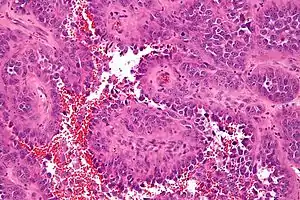

![]() Мікрофотознімок ангіосаркоми (фарбування г-е). Мікрофотознімок ангіосаркоми (фарбування г-е). | |